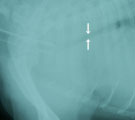

受診時。重度の呼吸困難。首を伸ばして両前足を立てている。 ステント設置前。胸部気管が扁平化。左には気管チューブがみえる。 ステント設置3日後。胸部気管がステントにて開大している。 6日後。呼吸は安静となり、じっと立てるようにはなった。この日に退院。

経過:8月初旬の猛暑時に来院。受診時、体温40.3℃。パンティングとチアノーゼを示す喘鳴症状がみられた。ただちに流水で体を冷やし30分後に35.8℃まで体温が下がったが、喘鳴・呼吸困難症状が続いた。心疾患の既往はなく気管虚脱が疑われた。酸素室中でも呼吸困難を示した。緊急にシリコンチューブにて気道拡張用ステントを作成し、100%酸素吸入全身麻酔下においてステント挿入による気管拡張術を行った。透視下にて胸部気管の扁平化を確認しその部位にステントを設置した。その後、気管支鏡でステント後方の気道に問題ないことを確認した。翌日、呼吸は安静化し夕方には自分で食事を食べるようになった。しかし体を動かすと喘鳴が始まった。6日後には立っても呼吸が安静でいられるようになり退院となった。